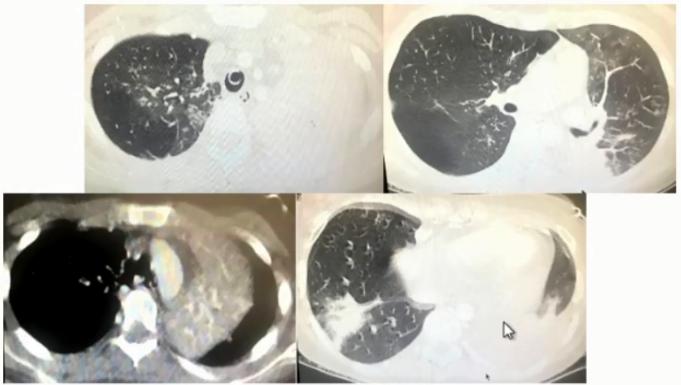

病例3

男,37岁,既往身体健康。因发热、咳嗽、咳黄痰1周入院。

日最高体温38.8℃-39.5℃,伴咽痛、肌痛、全身乏力,急诊血常规

WBC:8.74×109/L,N:0.865,予退热胶囊、头孢曲松、阿奇霉素等药物治疗3天无效。

CRP 12.10 mg/dl、PCT 0.107 ng/ml。

血清肺炎支原体抗体、肺炎衣原体抗体、军团菌抗体、流感病毒IgM均阴性。RT-PCR肺炎支原体核酸阳性。使用莫西沙星治疗14天后出院。

图3 双肺弥漫性小结节为主,中下肺布满粟粒样小结节,部分融合成片状

病原学诊断和转归

1. 病原学诊断

(1)入院次日BALF肺炎支原体核酸阳性

(2)血清肺炎支原体抗体,入院前为小于1:40;入院第14天为1:1280。

2. 转归

莫西沙星单药治疗2周后肺部阴影明显吸收

3. 诊断治疗面临的困难

• 临床表现不典型:咳黄痰

• 特殊的影像表现:中下肺弥漫小结节影

• 早期病原学检测无阳性发现

• 常规经验性治疗无效